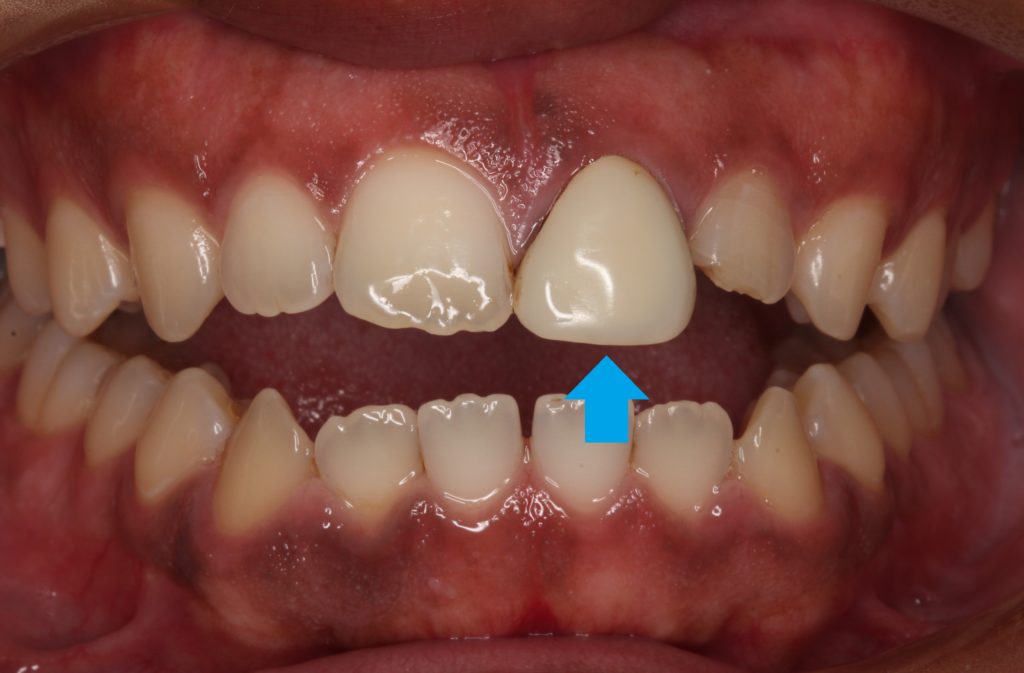

パッと見て前歯が1本浮いているのが分かります。

この歯ですね。

形も丸すぎていますし、色も白く、天然の歯のような透明感がありません。

このかぶせ物(クラウン)は保険の人工歯で、レジン前装冠というかぶせ物です。

表面の白く見えるのはレジンというプラスティックで、内部と裏側に金属が使われています。

現在も保険適応で製作される前歯のかぶせ物です。

レジンを使っているので透明感が無く、塗ったような単色の仕上がりで、経年劣化で変色をします。

今回の人工歯は色も形も全然合っていないものが入っています。